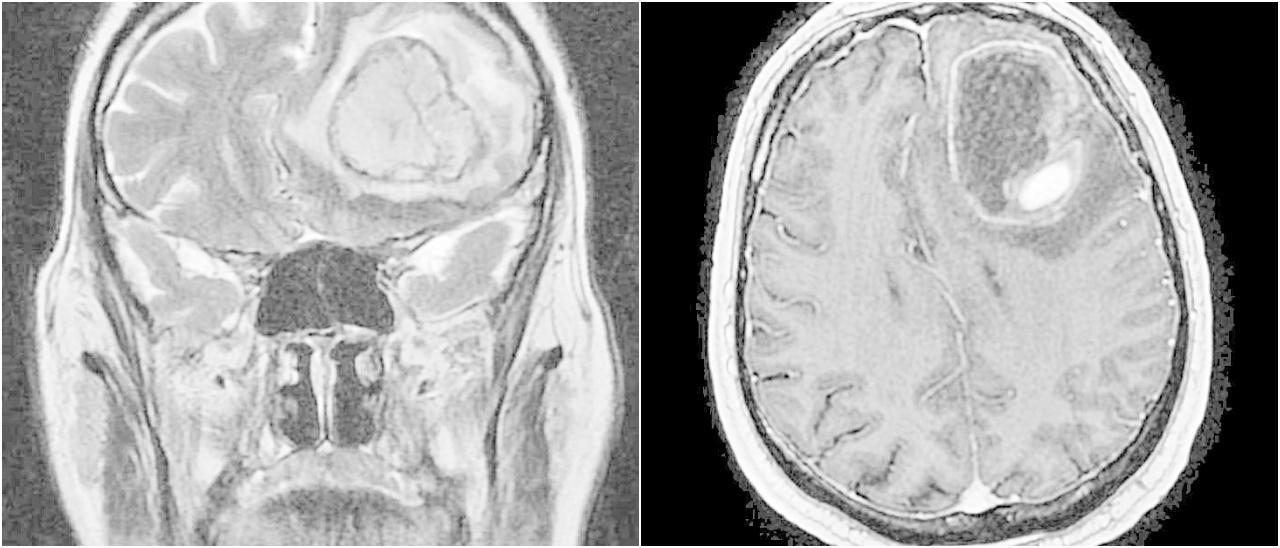

Imagen de una metástasis cerebral a nivel frontal izquierdo.